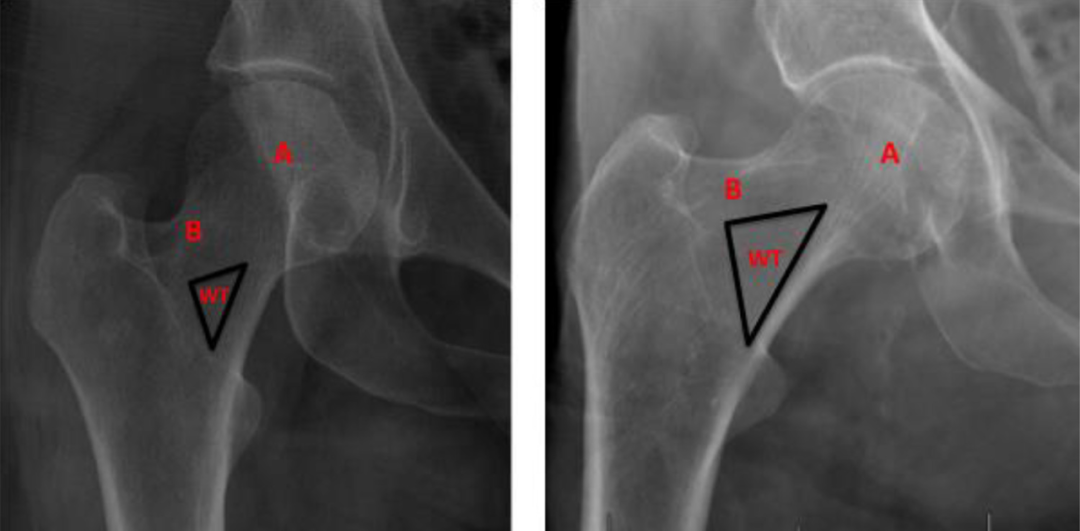

股骨颈内包含抗压与抗拉骨小梁,它们围成Ward三角。该三角上界为抗拉骨小梁,内下界为抗压骨小梁,是骨密度较低的区域(图1)。近期研究表明,骨小梁退化与股骨颈骨折发生密切相关,而Ward三角扩大则与股骨粗隆间骨折相关。

图1. (左)一位30岁女性患者的右髋X光片。(右)一位98岁男性患者的右髋X光片。注意右图中Ward三角(WT)的大小明显大于左图,并且与左图相比,右图中主要抗压骨小梁(A)和主要抗拉骨小梁(B)的退变更明显。